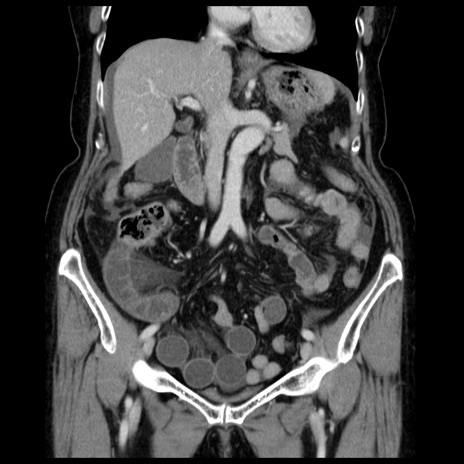

症例13(冠状断像)

【症例】70歳代女性

【主訴】腹痛、嘔吐

【現病歴】15時間程前(昨晩)より腹痛あり。今朝になっても症状の改善なく、嘔吐あり。腹痛も増悪あり、救急外来受診。

【既往歴】子宮癌全摘術後

【身体所見】意識清明、BP 121/72mmHg、P 74bpm、SpO2 100%(RA)、腹部:平坦・軟、腸雑音ほぼ聴取せず。下腹部・心窩部・臍左上に圧痛あり。反跳痛なし。

【データ】WBC 10600、CRP 0.15